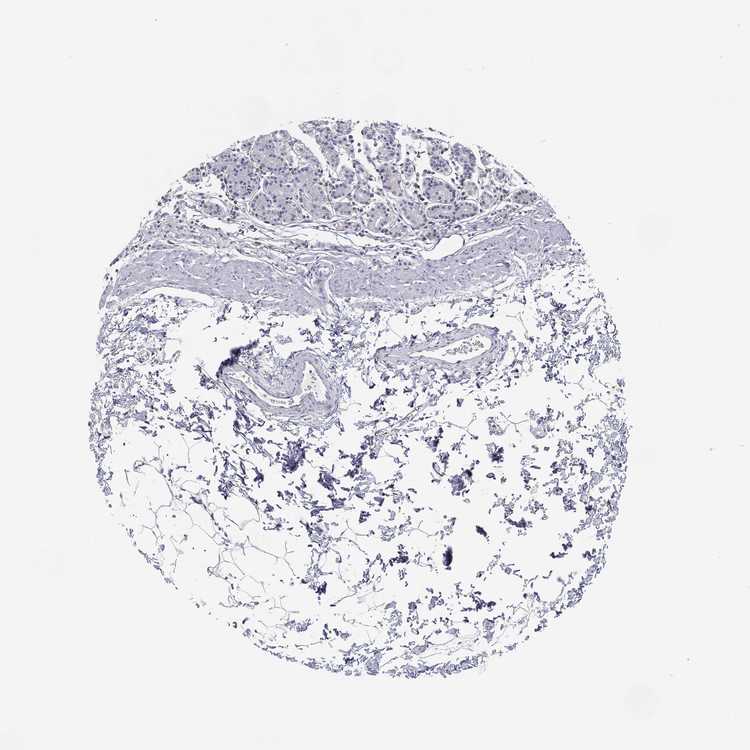

STOMACH 1 - Antibody stainingi

Antibody staining in the annotated cell types in the current human tissue is reported as not detected, low, medium, or high, based on conventional immunohistochemistry profiling in selected tissues. This score is based on the combination of the staining intensity and fraction of stained cells.

Each image is clickable and will lead to virtual microscopy that enables deeper exploration of all samples and also displays staining intensity scores, fraction scores and subcellular localization as well as patient and tissue information for each sample.

Antibody HPA069062Antibody CAB002431

Glandular cells Not detectedNot detected